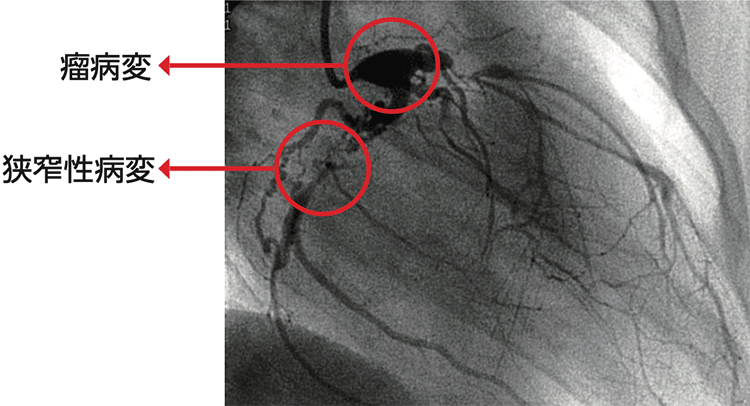

川崎病後冠動脈障害は、冠動脈瘤や冠動脈狭窄が混在し、また病変が多枝にわたり出現することも多く、複雑な血行動態をきたすことも、まれではありません(図1)。このような複雑な病変を評価するためには、冠動脈造影検査による形態診断のみでは不十分であり、冠動脈の血行動態の評価が、その後の治療を行ううえで必要です。